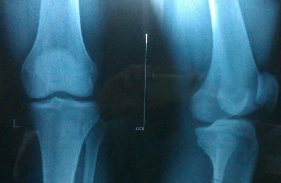

骨龄鉴定